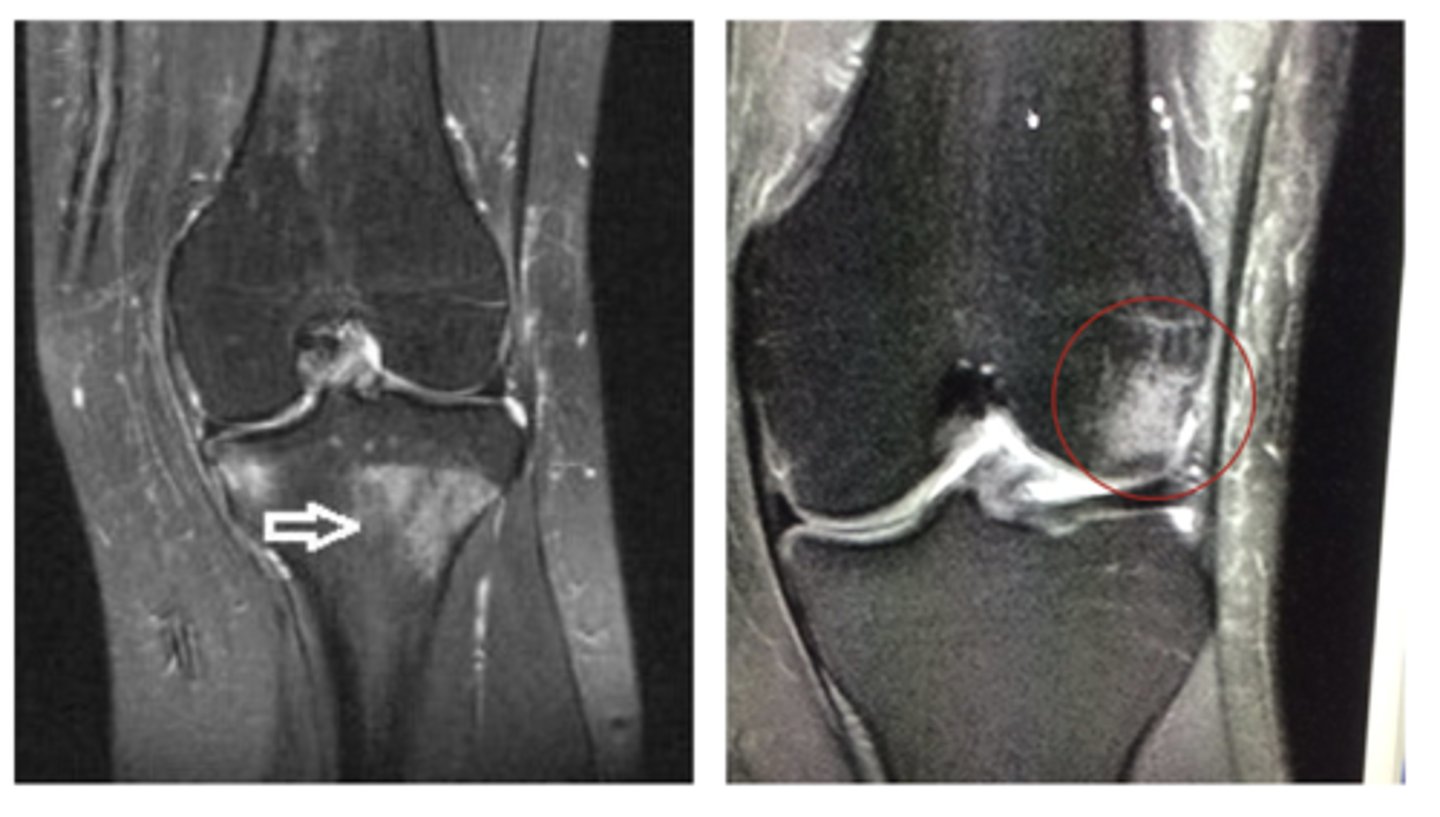

Sub-chondral edema/bone bruise (HUGE influence on rehab!!)

Define the pathology.

Synovitis surrounding the joint

Bone edema/bone bruise